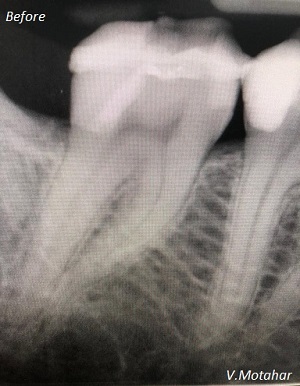

Root canal treatment on three rooted tooth! which had 4 canals!